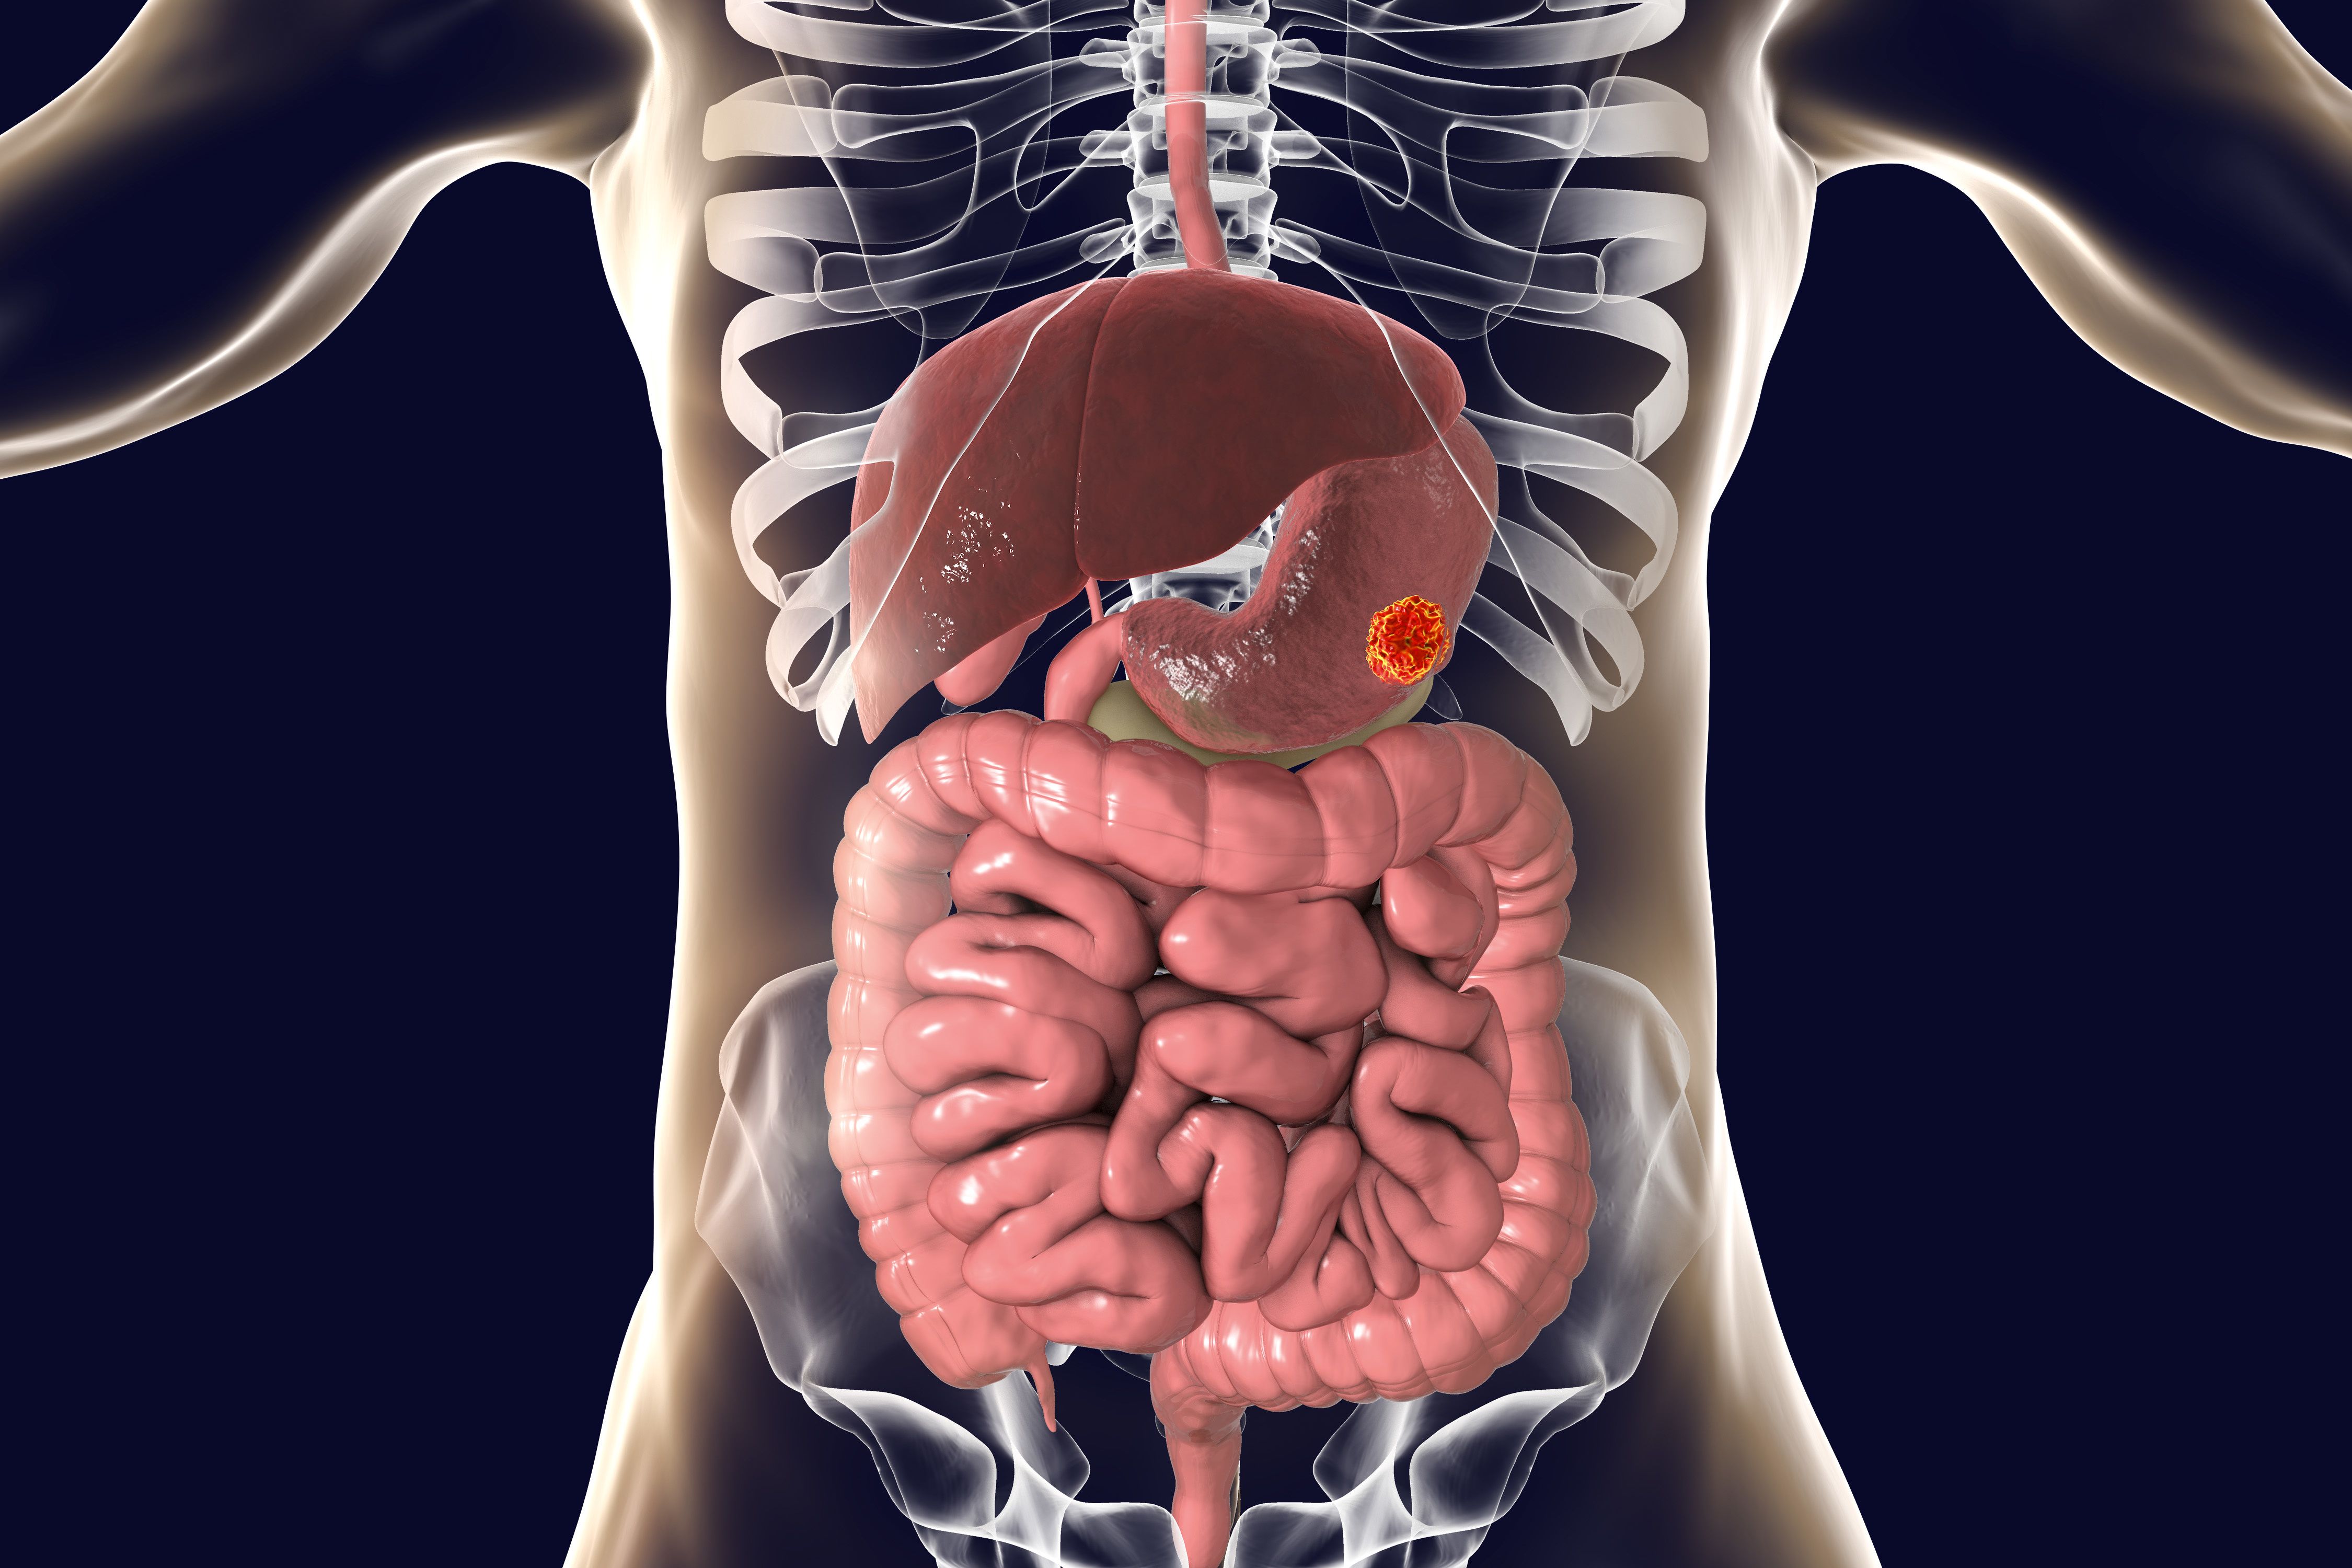

Early Data May Show PFS Benefit With Cancer Vaccine in Metastatic CRC

April 13th 2024Patients with metastatic microsatellite stable colorectal cancer treated with a personalized neoantigen cancer vaccine after chemotherapy demonstrated an early trend towards a progression-free survival benefit.